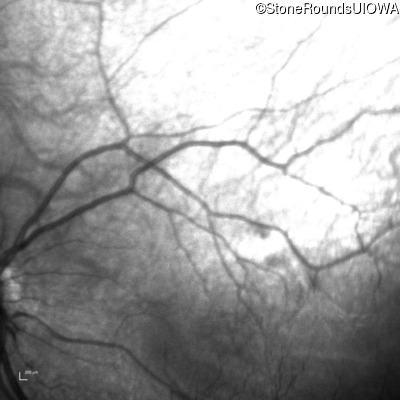

Infrared Fundus Photograph - Right - 20/2000

Exemplar

Infrared Fundus Photograph - Left - 20/80